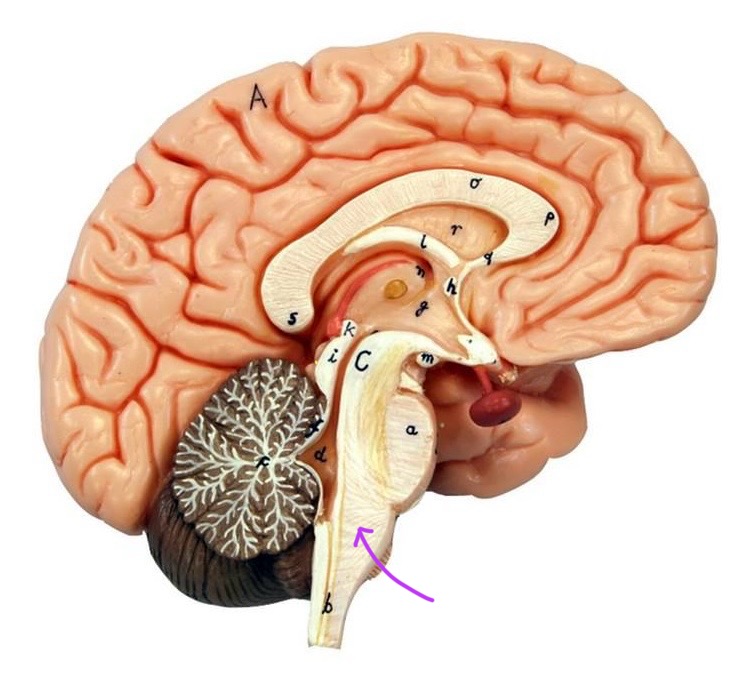

What is B?

cerebral aqueduct

What is below A at the very end?

central canal (spinal cord)